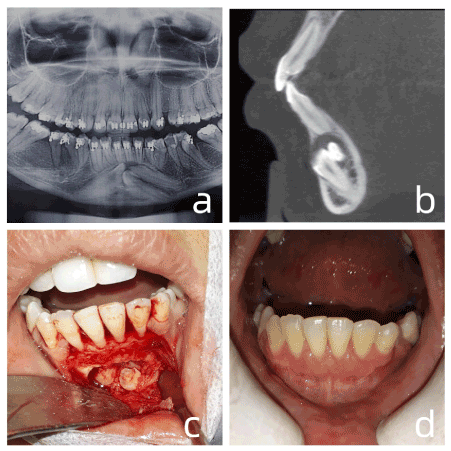

A female patient, 25 years old, leukoderm, was referred for evaluation of possible supernumerary teeth and revealed the presence of 3 supernumerary teeth in the mandibular symphysis region figure 3a. However, a panoramic examination did not provide information concerning the vestibulo-palatal positioning of the teeth, a CBCT was requested for better evaluation. Analyzing the 3D results in detail, the presence of a thick hair follicle associated with the supernumeraries was evidenced, which indicated the need for extraction. In the parasagittal section (Figure 3b) the presence of all supernumeraries by the buccal was revealed, in addition, external root resorption of tooth 31 was observed. Anesthesia was performed in the bottom of the buccal sulcus in the region of the mental foramen, bilaterally, and to the lingual gingiva in the lower incisor region. A #15 blade incision was made in the sucular region; mesial of tooth 33 to mesial of tooth 43, followed by two relaxing incisions in mesial of tooth 33 and mesial of tooth 43, featuring a quadrangular flap. Following the CBCT, the initial osteotomy was performed at 20 mm from the bony crest in the region of tooth 41, at high rotation with a spherical #6 drill. Upon exposing the crown, odontosections were started with a #703 tapered cone drill to minimize bone wear (Figure 3c). When the first supernumerary was extracted, it was possible to remove the enlarged hair follicle, again suggested by CBCT. The extraction of the other two supernumeraries followed the same protocol as the first, minimizing osteotomies and maximizing odontosections. At the end of the extractions, abundant irrigation with saline was performed, followed by suture with absorbable suture thread, the suture initially at the angles of the relaxants to avoid dehiscence of the suture, and continuing in the interdental papillae, and ending on the long relaxants axis. The postoperative period, 1 month after the surgery passed without periodontal gingival sequelae (Figure 3d).

Figure 3. a. initial panoramic radiograph. b. parasagittal section showing external root resorption of 31. c. sequential odontosections to minimize bone wear. d. one month after surgery

The CBCT performed for case 3 was also decisive for locating the supernumerary teeth, since it was possible to reveal their location by the vestibular, in addition to the exact point to begin osteotomy and prevent unnecessary bone wear.

In view of this, CBCT, to clearly visualize the extent and degree of external resorption present in tooth 31, was essential in Case 3, likely caused by the peri-coronary dental follicle of one of the supernumerary teeth. This type of advantage was confirmed in a study by Carolina S. Lai et al. [13], where 134 included canines were evaluated by CBCT, and it was shown that the case agreements regarding the presence and degree of resorption were greater when the evaluators used CBCT in comparison with conventional radiographic methods.